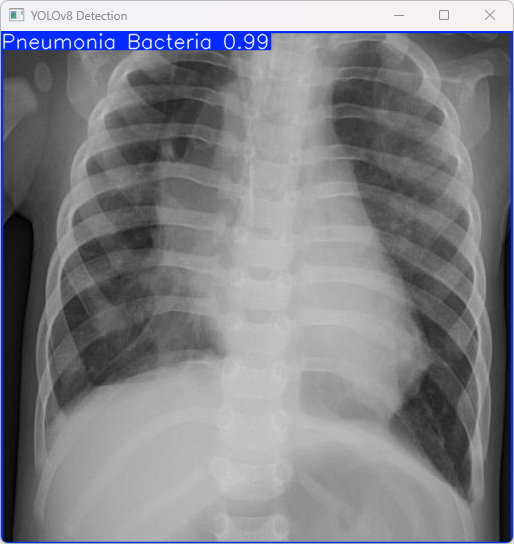

执行imgTest.py代码后,会将执行的结果直接标注在图片上,结果如下:

此段输出基于YOLOv8模型对图片'imagetest.jpg'执行了检测操作,并详细信息将在此处呈现

图像信息:

(1)处理的图像路径为:TestFiles/imagetest.jpg。

(2)图像尺寸为640×640像素。

检测结果:

(1)检测到图像属于 “Pneumonia Bacteria” 类别(细菌性肺炎)

处理速度:

(1)预处理时间: 7.0 毫秒

(2)推理时间: 4.5 毫秒

(3)后处理时间: 63.8 毫秒

总结:

该模型能够准确鉴别出细菌性肺炎于其他类型的肺炎,并且具有高效的推理机制。该系统便于实现快速诊断并具备潜在的实际应用价值。